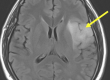

Εικόνα 2: Αριστερά, φυσιολογική μαγνητική τομογραφία (a-c) όπου φαίνεται ότι δεν υπάρχει πίεση επί του νωτιαίου μυελού και τα νευρικά δεμάτια (έγχρωμη εικόνα) δεν είναι συμπιεσμένα. Δεξιά, αυχενική μοίρα με εικόνα σπονδύλωσης και πίεση του νωτιαίου μυελού.